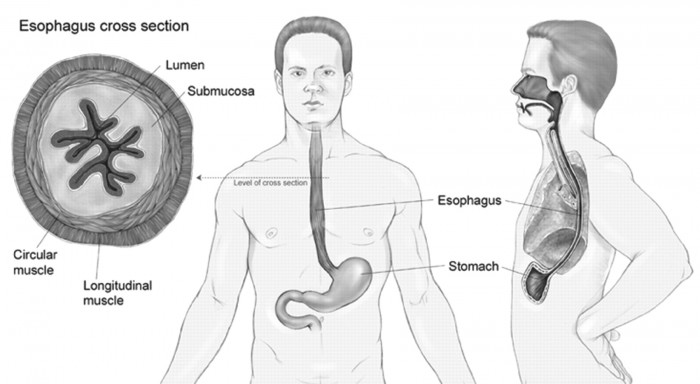

1 Esophagectomy:

This is a key surgery that is very risky due to the rebuilding of the region between the stomach and the vigorous piece of the esophagus. Risks are available as seepage of the fluid from the stomach or esophagus when the new bond was made.